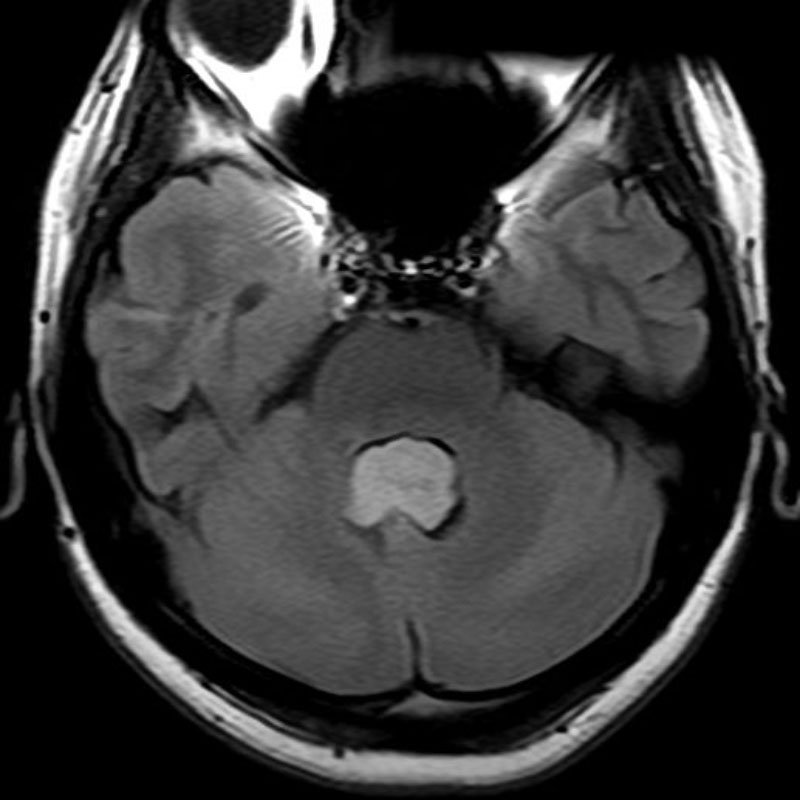

脳動脈瘤(Acom)

クリッピング術

松田/濵田/元永